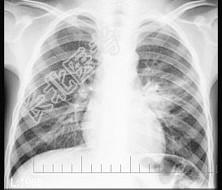

- 单项选择题3岁男孩,咳嗽、低热2周, 不咯血、咳痰,X线检查如图, 最可能的诊断是 ( )

A、左肺炎症

B、左肺结核(Ⅰ型)

C、左肺结核(Ⅱ型)

D、左肺结核(Ⅲ型)

E、左肺癌